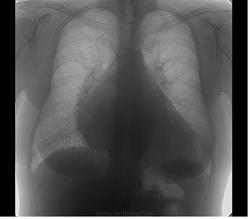

Пол пациента: Женский пол Тип патологии: Другое Область исследования: Средостение и сердце Методы исследования: Rg https://radiomed.ru/sites/default/files/styles/case_slider_image/public/user/5536/2_1.jpg?itok=5gIAUs0v https://radiomed.ru/sites/default/files/styles/case_slider_image/public/user/5536/3_1.jpg?itok=DAF4_PHJ ID:21733 Чт, 14/06/2012 - 22:44 #1 И.Бондаренко Не на сайте Был на сайте: 1 день 12 часов назад Зарегистрирован: 13.09.2011 - 22:55 Публикации: 9213 Отдайте функционалам. Это их хлеб. Чт, 14/06/2012 - 22:46 #2 Mitkampfer Не на сайте Был на сайте: 11 лет 6 месяцев назад Зарегистрирован: 27.07.2010 - 07:43 Публикации: 1454 уже) Не ограничивайте свою мысль Живешь пока учишьсяEcrasez l’infame